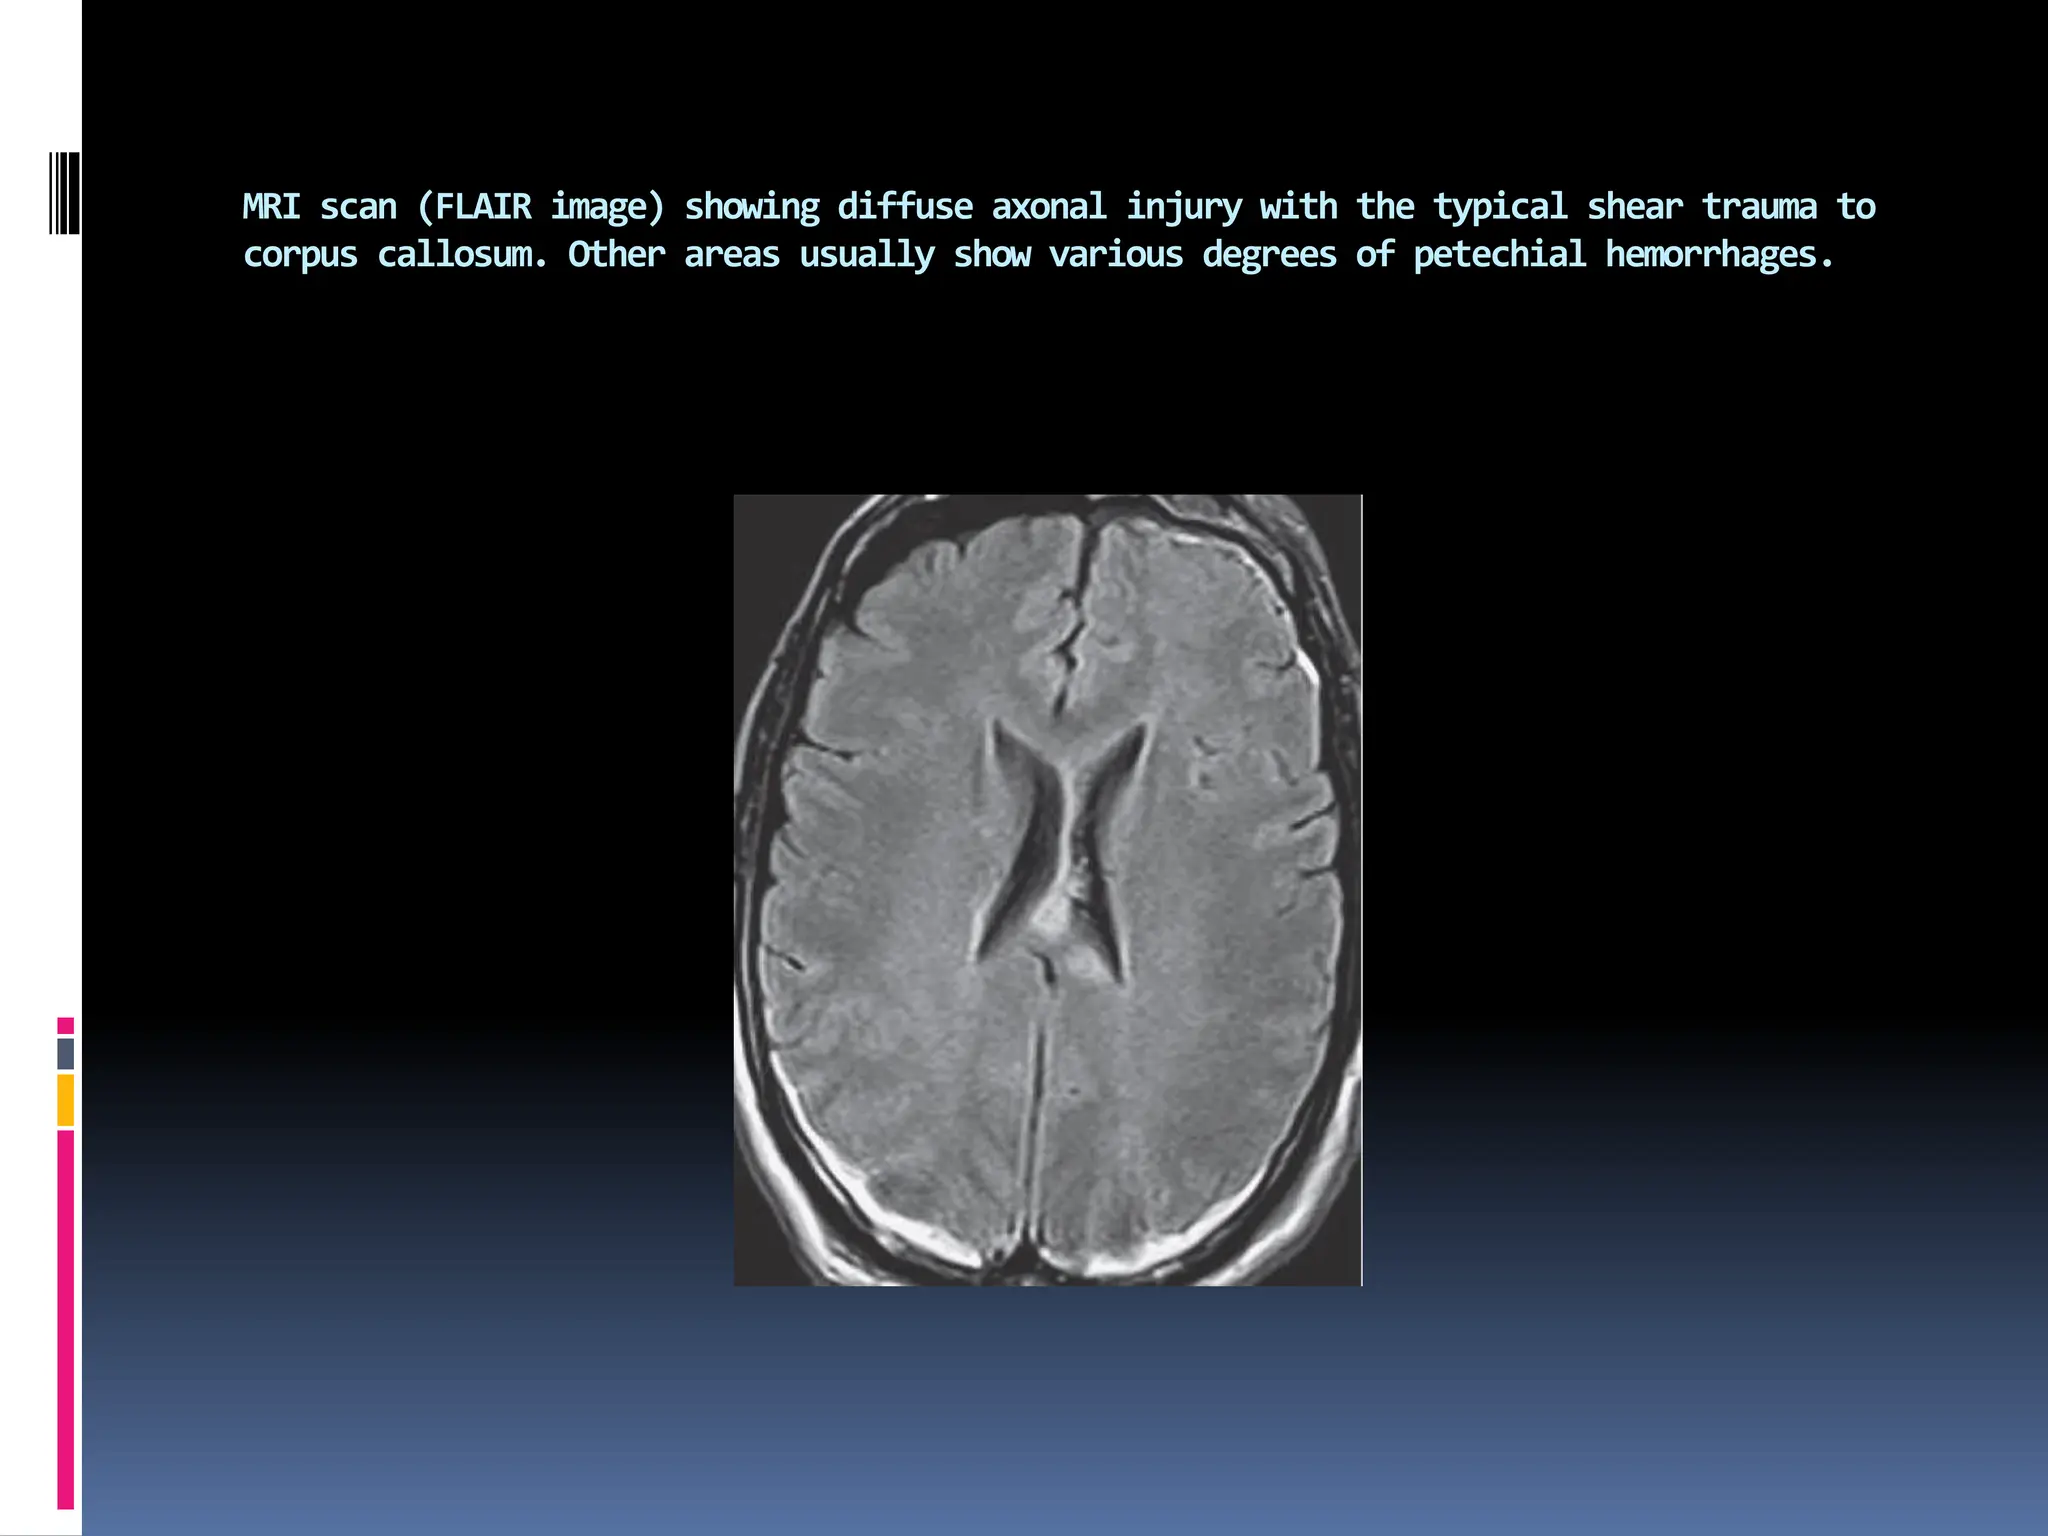

MRI scan (FLAIR image) showing diffuse axonal injury with the typical shear trauma to

corpus callosum. Other areas usually show various degrees of petechial hemorrhages.

▪ Diffuse axonal injury (DAI)

 Consists of scattered shearing of white matter axons,

histologically appearing days after injury as swollen retraction

balls of axoplasm.

 Their distribution is centripetal and magnitude related to the

force of injury.

 Extension of these white matter shearing lesions, from sites of

relative tethering such as the corpus callosum down into the

brainstem, is believed to represent an increasing degree of injury

related to rotational or angular acceleration–deceleration of the

skull and brain.

 Hemorrhages into the deeper gray matter or ventricles also often

signify DAI .